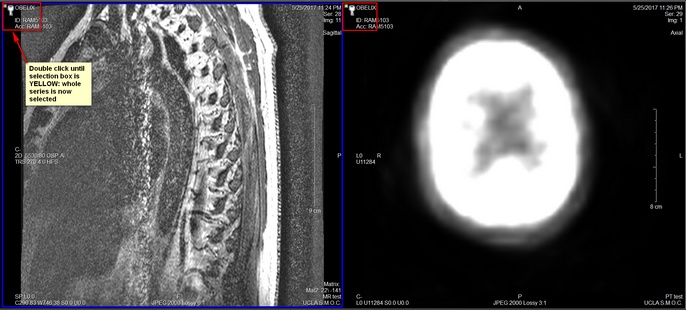

Select the whole series to be displayed in the Viewport.

To select all images in the Series for print, double click on the selection box until it is yellow.